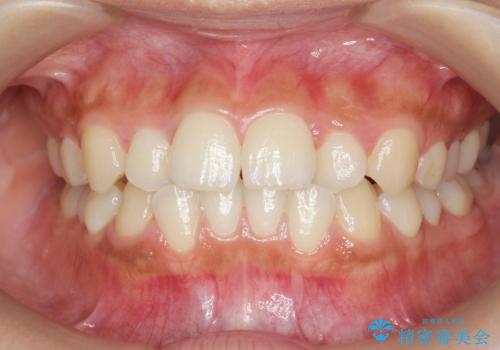

前歯のねじれ、すれ違いを改善 部分ワイヤー+マウスピース矯正

- 上下前歯のすれ違い、ねじれのある歯並びの矯正治療を求めて来院されました。

前歯のすれ違いが改善することで噛みやすくなった。と矯正治療の結果に満足いただくことができました。